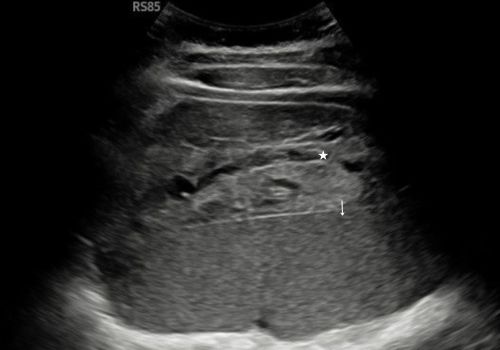

Figure 5 and 6 above; Heterogeneous area adjacent to the spleen with fluid demonstrates no colour doppler flow (arrow).